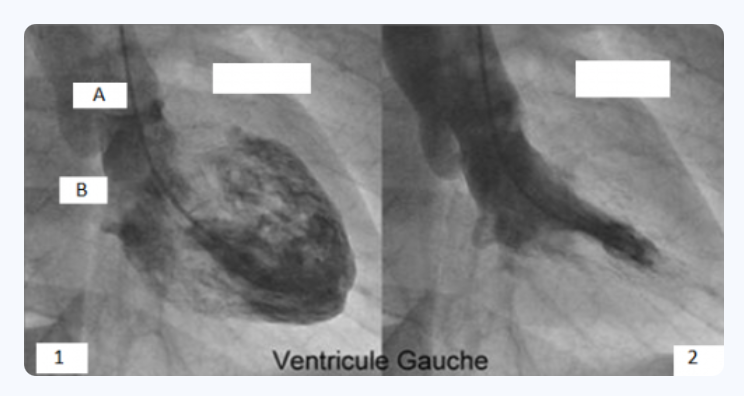

Concernant cet examen : (cf photo)

C’est bien une coronarographie.

Le B correspond à une diagonale !

A propos de cet examen : (cf photo)

A B

A propos de ces deux images :

ABE